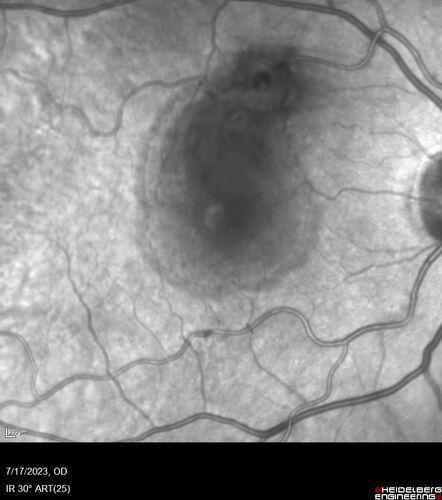

Retinal Arterial Macroaneurysm with pre-retinal hemorrhage

72 year old female who takes Xarelto had sudden vision loss while moving heavy furniture.  VA was 20/200.  The lesion has preretinal blood but later rebled with subretinal blood, was lasered and the final vision was not very good but the patient was lost to follow-up at 3 months